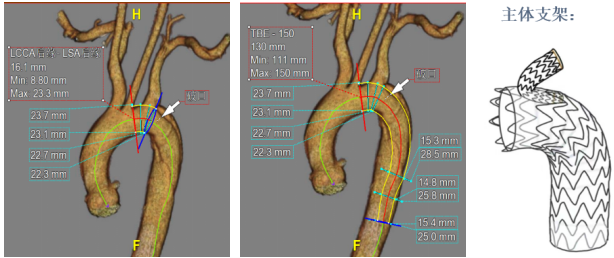

★ 病例3

27岁男性,急性主动脉夹层,破口紧邻左锁骨下动脉。

手术亮点:

TBE支架采用“导丝直出”设计,释放后无需解缠绕,操作简便;

支架柔顺性好,即使成角90°–180°也不打折;

顺应弓部运动,长期通畅率良好,五年随访结果优异。